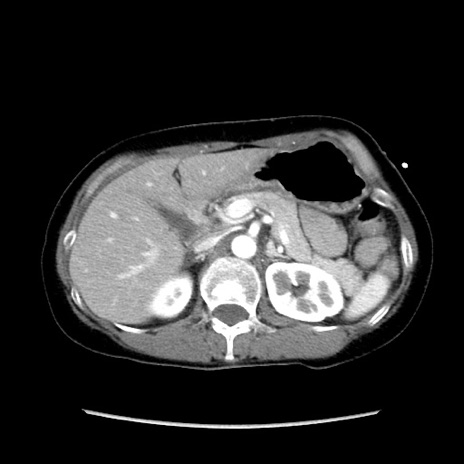

症例32(横断像)

【症例】40歳代 女性

【主訴】上腹部痛、嘔気・嘔吐

【現病歴】約9時間前頃から急に上腹部痛、嘔気、嘔吐が出現。改善しないため救急要請。

【既往歴】子宮頚癌(広汎子宮全摘術、放射線療法)、腸閉塞

【身体所見】腹部:平坦、軟、腸雑音亢進、上腹部を中心に腹部全体に圧痛あり。

【データ】WBC 8400、CRP 0.03